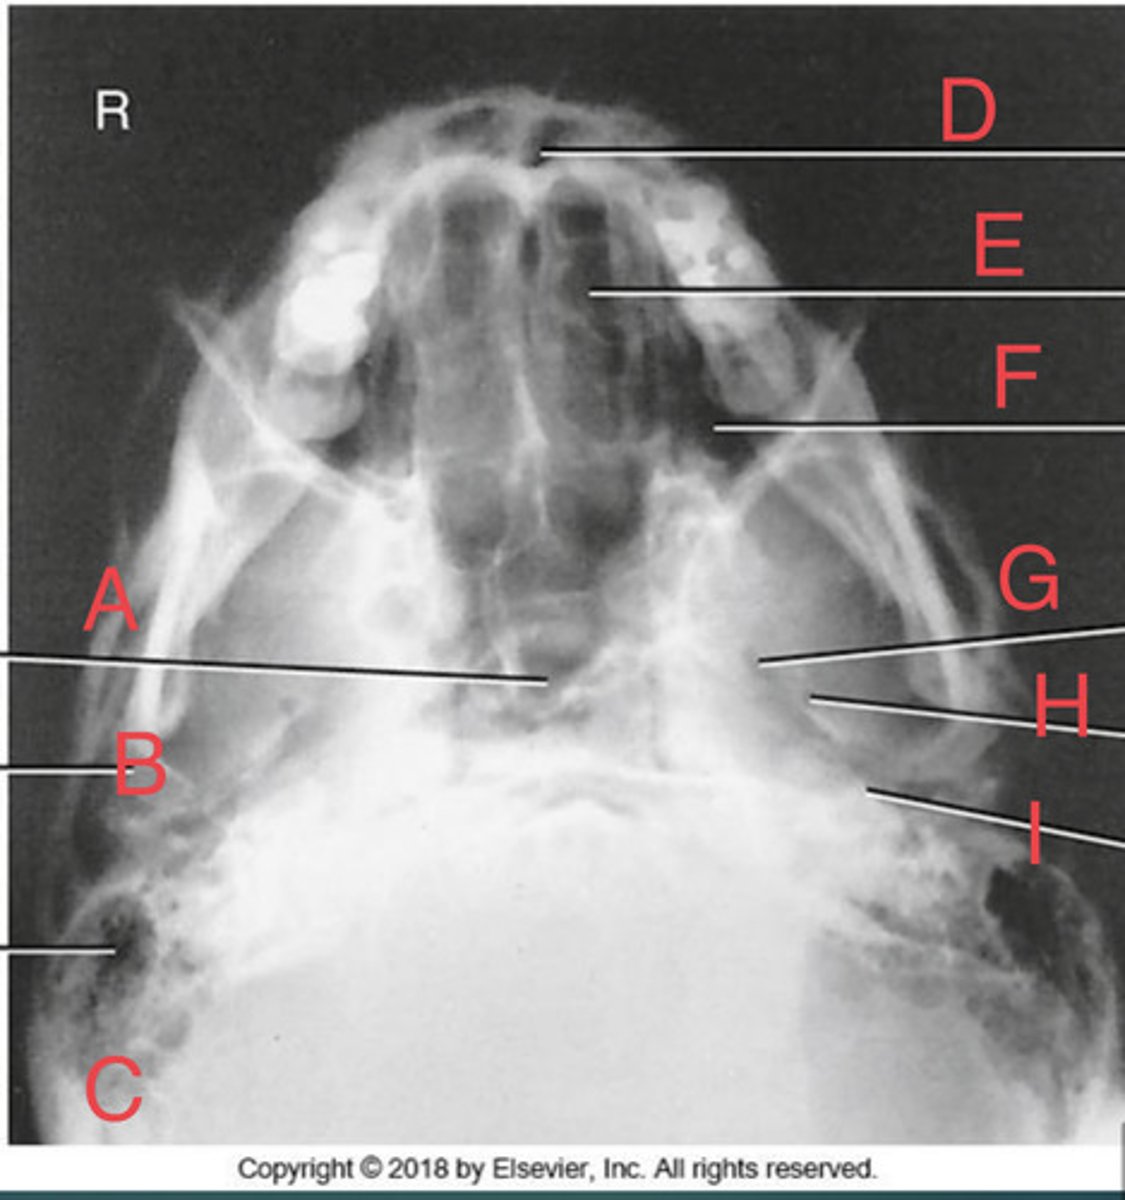

SMV sinuses

What position?

Sphenoid sinus of sphenoid bone

A.

R mandibular condyle of mandible

B.

R Mastoid air cells of temporal bone

C.

Nasal fossa

D.

L. Ethmoid sinus of ethmoid bone

E.

L maxillary sinus of maxilla

F.

L foramen ovale of sphenoid bone

G.

foramen spinosum of sphenoid bone

H.